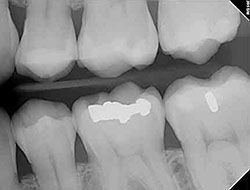

Digital X-rays

Services provided by General Dentists.

Digital X-rays provide several imaging options that are designed to save time, provide clearer dental photos.

Our practice is focused on making your dental experience as comfortable as possible. At your next appointment, we’ll be happy to answer any questions you may have.